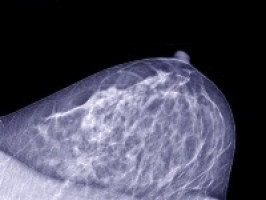

The UK's National Institute for Health and Clinical Excellence (NICE) has announced new guidelines for the NHS for people with a family history of breast cancer.

Surveillance for people with a personal history and a family history of breast cancer:

Offer annual MRI surveillance to all women aged 30–49 years with a personal history of breast cancer who are at high risk of contralateral breast cancer or have a BRCA1 or BRCA2 mutation.

Offer annual mammographic surveillance to all women aged 50–69 years with a personal history of breast cancer who are at high risk of contralateral breast cancer or have a BRCA1 or BRCA2 mutation.